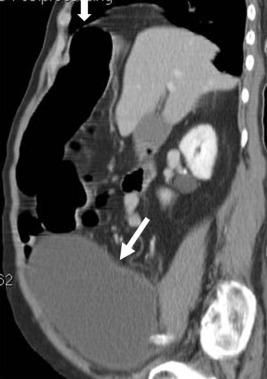

A 77-year-old man with a history of benign prostate hypertrophy and ischemic heart disease was referred to our emergency department because of progressive abdominal distension, constipation, and leg edema for 1 week. There was no abdominal pain, fever, nausea, vomiting, body weight loss, or dyspnea. The patient had poor appetite and decreased urine output in the past week. On physical examination, the body temperature was 36.6°C. The bowel sound was hyperactive. Distended abdomen without tenderness was detected. Digital examination revealed an enlarged prostate. A kidney ureter bladder radiograph (Fig. 1 ) revealed a large radiopaque lesion with markedly dilated colon loops at the transverse segment, and the hepatic and splenic flexures.

Kidney ureter bladder radiograph.

Figure 1.